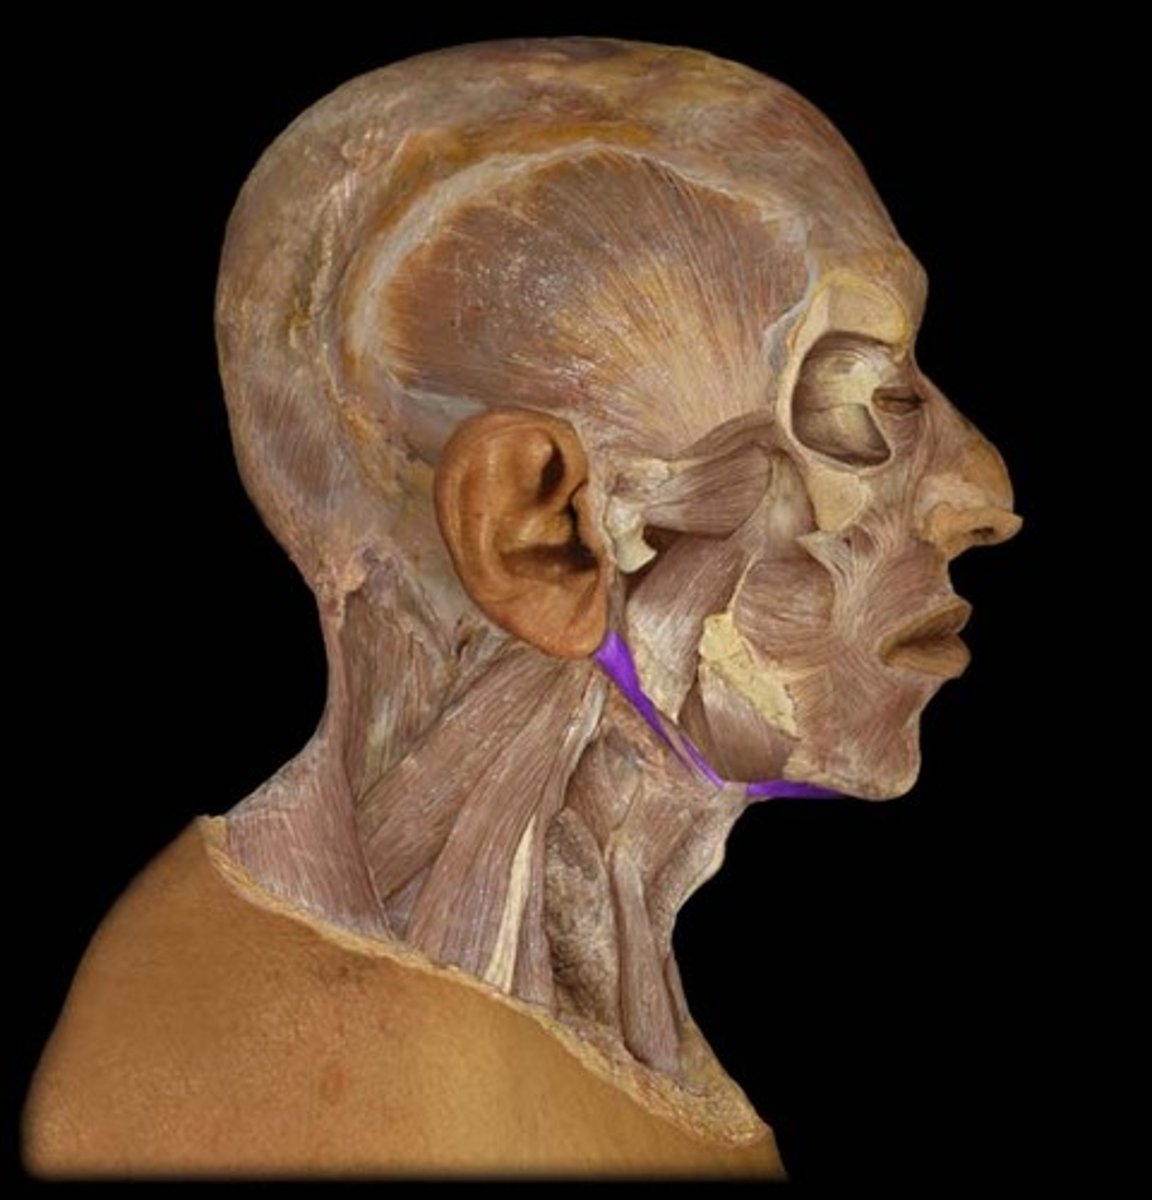

Temporalis

Origin: Temporal Lines and Temporal Fossa of Cranium

Action: Elevation of Mandible

Masseter

Origin: Zygomatic Arch

Action: elevates mandible

Platysma

Origin: Fascia of deltoid and pectoralis major

Insertion: Mandible, skin and subcutaenous tissue of lower face

Action: depresses mandible, draws angle of mouth downward (pout), tightens skin of the neck

Digastric

Origin: Anterior Belly: Diagastric fossa of mandible: mastoid process of temporal bone

Insertion: Hyoid one via fascial sling

Action: depresses mandible, opens the mouth (when hyoid bone is fixed)

Stylohyoid

Action: elevates hyoid bone

Origin: styloid process of temporal bone

Insertion: hyoid bone